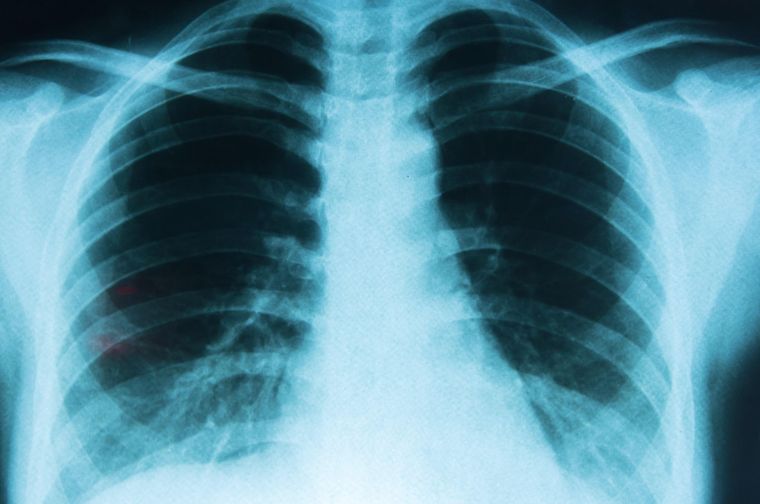

Tamizaje: detectar antes para vivir más y mejor

El tamizaje del cáncer de pulmón es una estrategia en expansión en el mundo y una herramienta fundamental para reducir la mortalidad. Su objetivo es diagnosticar la enfermedad en estadios tempranos, cuando el tratamiento puede ser más efectivo y hasta curativo.

Dentro del tamizaje, la herramienta más utilizada es la tomografía computada de baja dosis (TCBD), un estudio rápido, sin dolor y de alta precisión que permite detectar lesiones pulmonares muy pequeñas, incluso antes de que aparezcan síntomas. En Argentina, el Consenso Nacional sobre Tamizaje de Cáncer de Pulmón recomienda realizar este estudio una vez por año en personas de 55 a 74 años con alto riesgo: fumadores o exfumadores con un consumo acumulado de al menos 30 paquetes al año, que hayan dejado de fumar en los últimos 15 años y no presenten enfermedades graves.

Diversos estudios demostraron que este tipo de control puede reducir la mortalidad por cáncer de pulmón hasta en un 20% y que el diagnóstico precoz no solo mejora la calidad de vida de las personas, sino que también reduce los costos del sistema sanitario, dado que tratar la enfermedad en etapas avanzadas puede ser hasta diez veces más costoso.